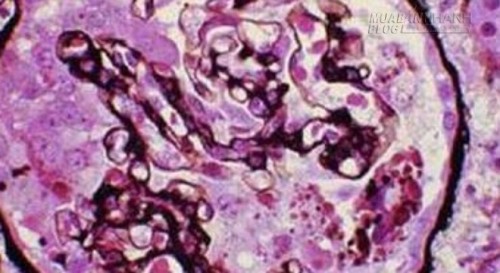

Viêm cầu thận là một loại bệnh thận. Viêm cầu thận khiến cho khả năng loại bỏ chất thải và dịch dư thừa của thận bị suy kém.

Viêm cầu thận có thể xảy ra cấp tính hoặc mãn tính. Viêm cầu thận có thể tự xảy ra (viêm cầu thận tiên phát) nhưng cũng có thể bắt nguồn từ 1 căn bệnh nào đó như bệnh tiểu đường, lupus (viêm cầu thận thứ phát)